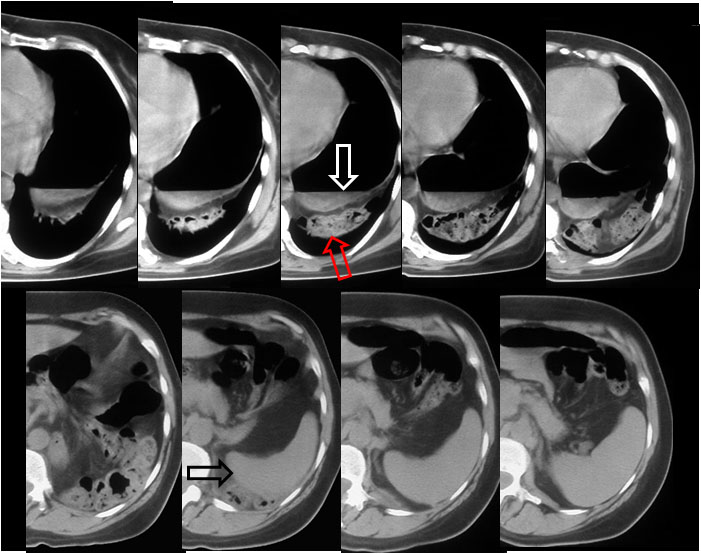

SIGNO DE LA SILUETA DEL CATÉTER

Signo útil para identificar la posición de un catéter de drenaje pleural en la radiografía anteroposterior de tórax. Es, en realidad, una variante del signo de la silueta.

A veces, la situación anómala de un catéter mal colocado puede pasar desapercibida en la radiografía. Si el catéter está en la cavidad pleural, rodeado de aire libre o de pulmón bien ventilado, tendrá unos márgenes bien definidos. Pero si el tubo está en las partes blandas de la pared torácica, la densidad similar de los tejidos blandos y del plástico de tubo hace que las paredes de éste no sean visibles.

En la imagen, margen nítido del catéter bien colocado (flechas).

Esquema que muestra un catéter situado en el espacio pleural en un paciente con neumotórax (izquierda) y en los tejidos blandos de la pared torácica (derecha). En el primer caso el catéter se dibuja con nitidez; en el segundo, se pierde su contorno por el contacto con los tejidos blandos.